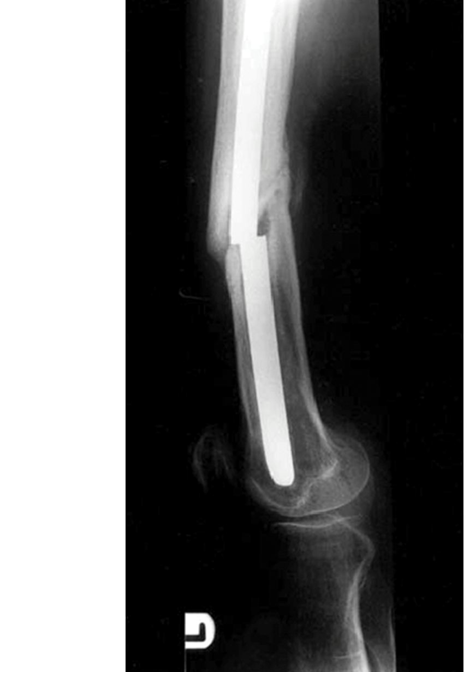

- Scaphoid Fractures: Advanced Clinical Guide to Anatomy, Biomechanics, & Management

- Mastering Carpal Fracture Fixation: An Intraoperative Guide to Non-Scaphoid Injuries